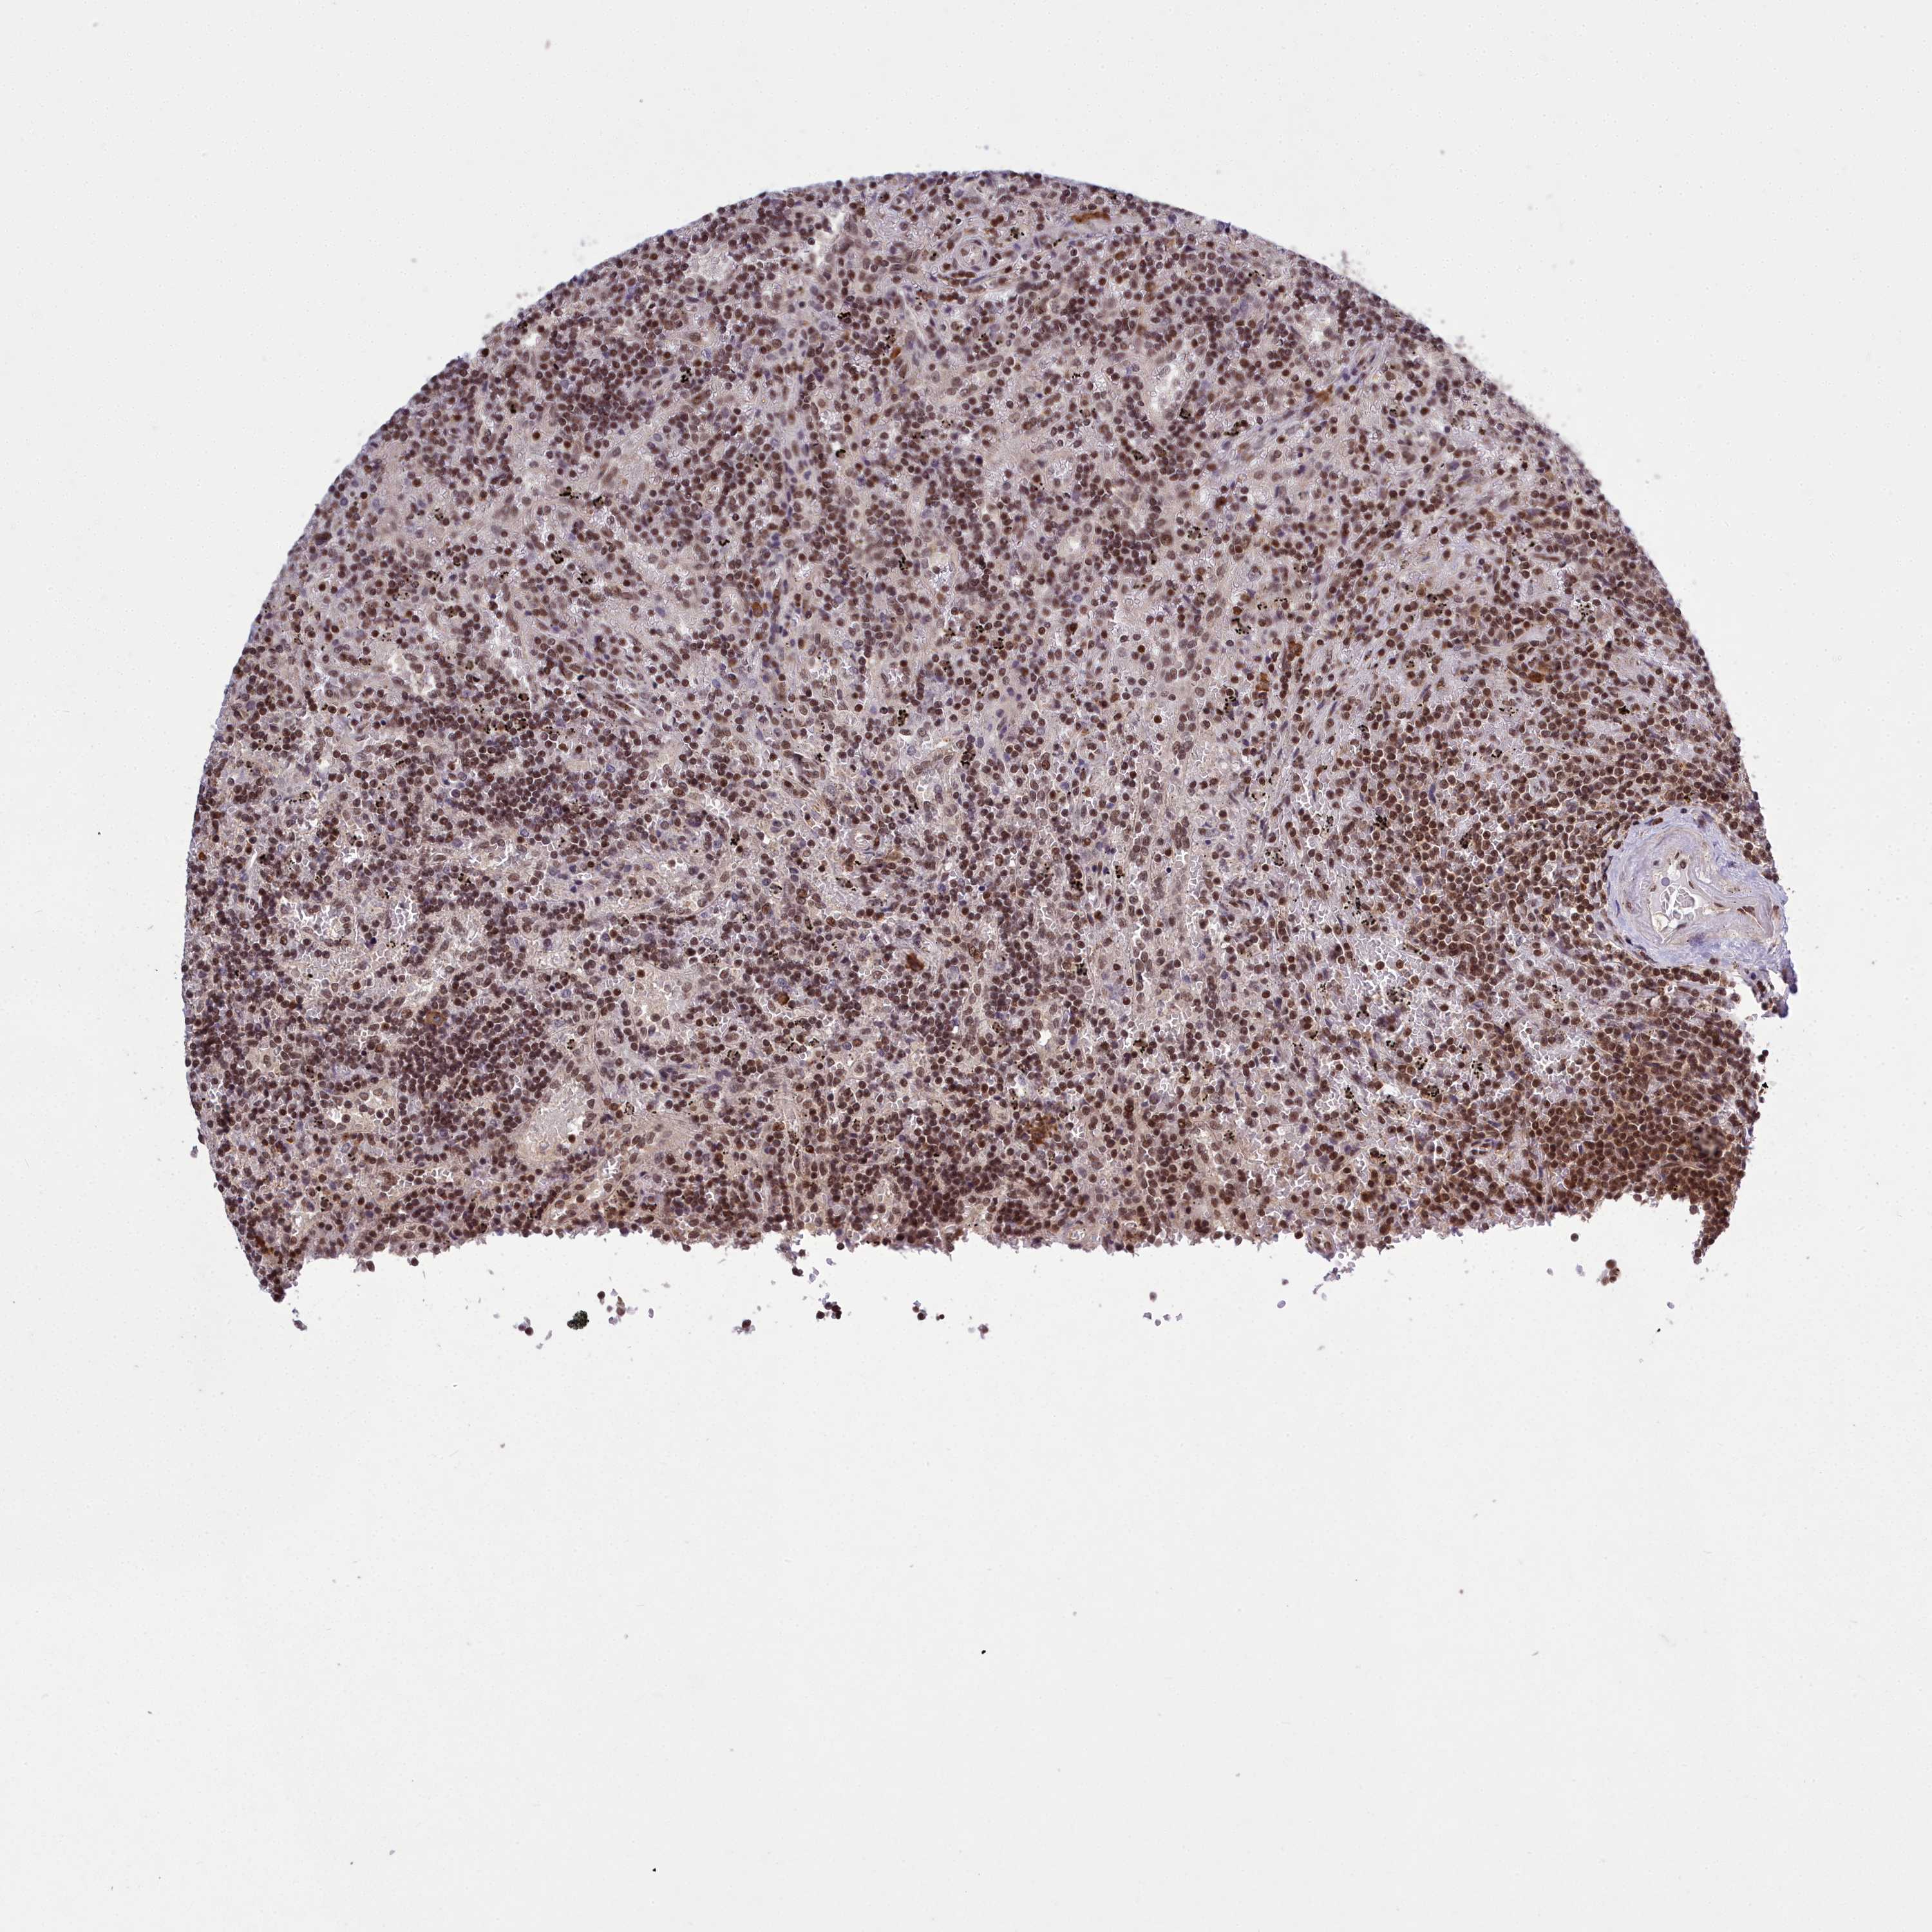

CANCER LYMPHOMA Show tissue menu

LYMPHOMA - Protein expressioni

A mouse-over function shows sample information and annotation data. Click on an image to view it in a full screen mode. Samples can be filtered based on level of antibody staining by selecting one or several of the following categories: high, medium, low and not detected. The assay and annotation is described here.

Each image is clickable and will lead to virtual microscopy that enables deeper exploration of all samples and also displays staining intensity scores, fraction scores and subcellular localization as well as patient and tissue information for each sample.

Antibody HPA044811

Staining

High

Intensity

Strong

Quantity

>75%

Location

Nuclear

Hodgkin's disease, NOS

Malignant lymphoma, non-Hodgkin's type, High grade

Malignant lymphoma, non-Hodgkin's type, Low grade